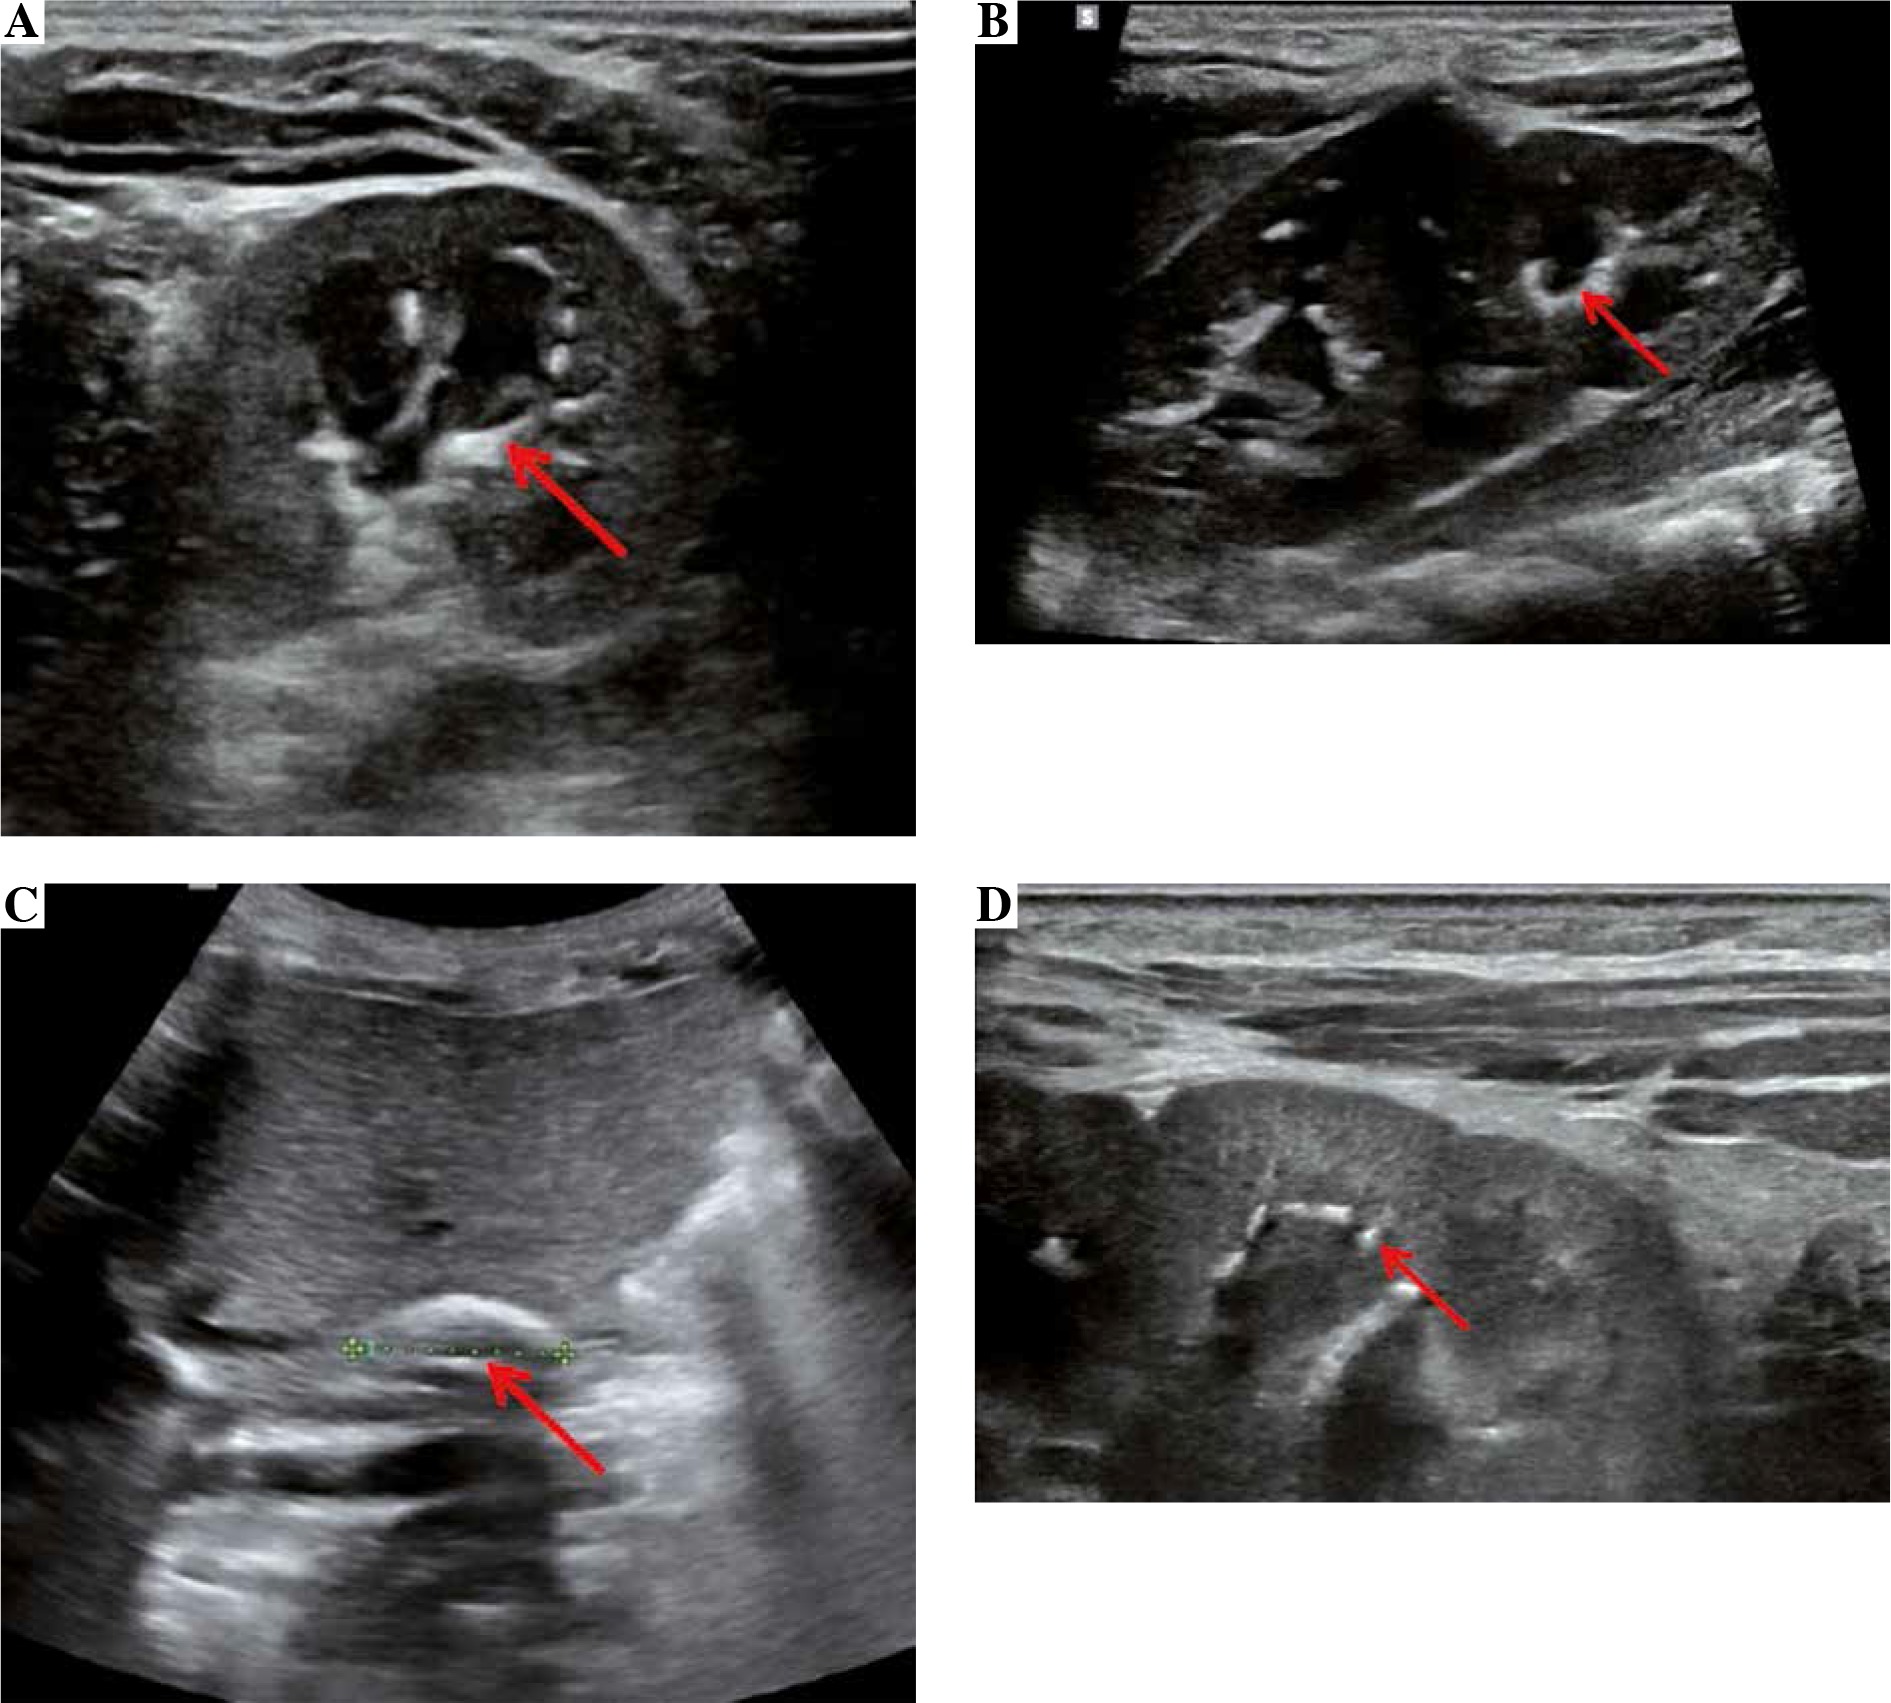

We present a case of a female infant born from second pregnancy (first pregnancy resulted in miscarriage in 20th week of gestation after abdominal injury), mother of Latin American descent, father of Polish origin. Negative family history of kidney diseases, calcium and phosphate homeostasis disorders, urolithiasis, systemic diseases, and thrombosis. The pregnancy was complicated by hypothyroidism, uterine myoma, urinary tract infections, and appendectomy at 16th week of gestation. Fetal ultrasound scan (US) performed repeatedly did not show any abnormalities, with normal image of the kidneys. The baby was born by caesarean section due to pre-labor rupture of the membranes, with a body weight of 3,570 γ and Apgar score of 10. The adaptation period was normal; the girl was vaccinated according to routine vaccination schedule and breastfed. At the age of 2 months, she was hospitalized in the city hospital due to bronchiolitis. The abdominal US showed kidneys 45 mm long with an abnormal image of the renal columns, with numerous hyperechogenic foci. Nephrocalcinosis was suspected and the infant was referred to our hospital. The girl was admitted at the age of 3 months in good general condition, no physical abnormalities, and arterial blood pressure of 77/36 mm Hg. Laboratory examination were as follows (reference ranges in brackets): WBC 8.06 × 103/µl (5.7-17), RBC 4.09 × 106/µl (3.2-4.3), PLT 415 × 103/µl (250-550), CRP < 0.5 mg/dl (≤ 1.0), creatinine 0.2 mg/dl (0.2-0.4), urea 14.0 mg/dl (2.2-27.8), calcium 10.5 mg/dl (7.7-11.5), phosphorus 7.2 mg/dl (2.5-7.0), alkaline phosphatase 281 U/l (80-345), 25(OH)D 20.4 ng/ml (20-50), parathyroid hormone 7.7 pg/ml (12-95); urinary crystallization ratio: calcium : creatinine ratio 0.43 (< 0.81), phosphorus : creatinine ratio 0.85 (0.3-1.2), magnesium : creatinine ratio 0.55 (> 0.1), magnesium : calcium ratio 1.29 (0.8-1.3). The results of urinalysis were within the normal range. In the ultrasound scan, numerous hyperechogenic foci in both kidneys were observed and nephrocalcinosis was suspected. Vitamin D3 supplementation was discontinued. After 3 months, serum phosphorus normalized (6.0 mg/dl), and 25(OH)D level was slightly below normal range (19.8 ng/ml). US showed right kidney 54 mm long, left kidney 62 mm long, linear calcifications along the pyramids visible in both kidneys, more lesions in the left kidney (Figs. 1A, 1B, 1D). Doppler scan showed lack of visible blood flow from the renal veins to IVC, with compensatory flow from the renal veins to the paravertebral plexuses; IVC obliteration, with a massive calcification in the hepatic section (Fig. 1C); minor linear calcifications in the liver caudate lobe at the point of contact with IVC. The connection between IVC and common iliac veins were not visible. The image suggested the history of extensive venous thrombosis. Magnetic resonance (MR) revealed no contrast flow in the iliac veins and IVC, compensatory venous outflow from the lower limbs and from the kidneys to the paravertebral plexuses (Fig. 2); in IVC, a segmental dilatation of 11 × 7 mm over a length of 23 mm spatially coincident with calcification described in the ultrasound scan. The results of coagulation system were as follows: INR 1.01 (0.9-1.2), kaolin-cephalin clotting time 34.62 s (28-40), fibrinogen 1.77 g/l (1.80-3.50), homocysteine 6.92 µmol/l (3.70-13.90), antithrombin III 96.3% (75-125), protein C 61% (50-125), protein S 67.36% (50-125), D-dimers 6893.06 µg/l (0-550). Leiden factor V mutation and c.20210G > A prothrombin gene mutation were excluded. Due to the increased concentration of D-dimers and obliterated IVC, low-molecular-weight heparin was administered at the therapeutic dose (nadroparin, 100 IU antiXa/kg once daily, subcutaneously). Anticoagulation was continued for 4 months. After a month of anticoagulation, D-dimer levels came back to normal (433.54 µg/l). Ultrasound scan performed at the age of 10 months showed: right kidney 60 mm long, left kidney 68 mm long, image of the venous system as in the previous study. The girl is currently 2 years old, develops according to age, and is under the care of a nephrology and hematology clinic. Obliterated venous vessels did not recanalize.